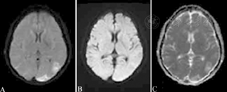

病例2:女性,39岁,因"胃癌术后4年余,头痛1周,右眼视力下降2 d"入院。既往无高血压史。发病前使用靶向药物阿帕替尼治疗6个月余。入院查体:血压160/110 mmHg,神志清楚,语言流利,双侧瞳孔等大等圆,直径2.5 mm,对光反射灵敏,眼底正常,右眼视力下降,四肢肌力正常,脑膜刺激征阴性,病理反射未引出。常规血液化验未见明显异常。头颅MRI示双侧顶枕叶信号异常,右侧明显,T1为等信号,T2及FLAIR高信号、DWI及ADC稍高信号(图2)。考虑化疗药物阿帕替尼引起PRES,停用阿帕替尼并控制血压后,头痛及视力下降症状好转出院。

患者女性,39岁,因"胃癌术后4年余,头痛1周,右眼视力下降2 d"入院,头颅MRI示双侧顶枕叶条状及片状异常信号,右侧明显,液体衰减反转恢复序列呈高信号(A),弥散加权成像呈稍高信号(B),表观弥散系数图呈稍高信号(C)